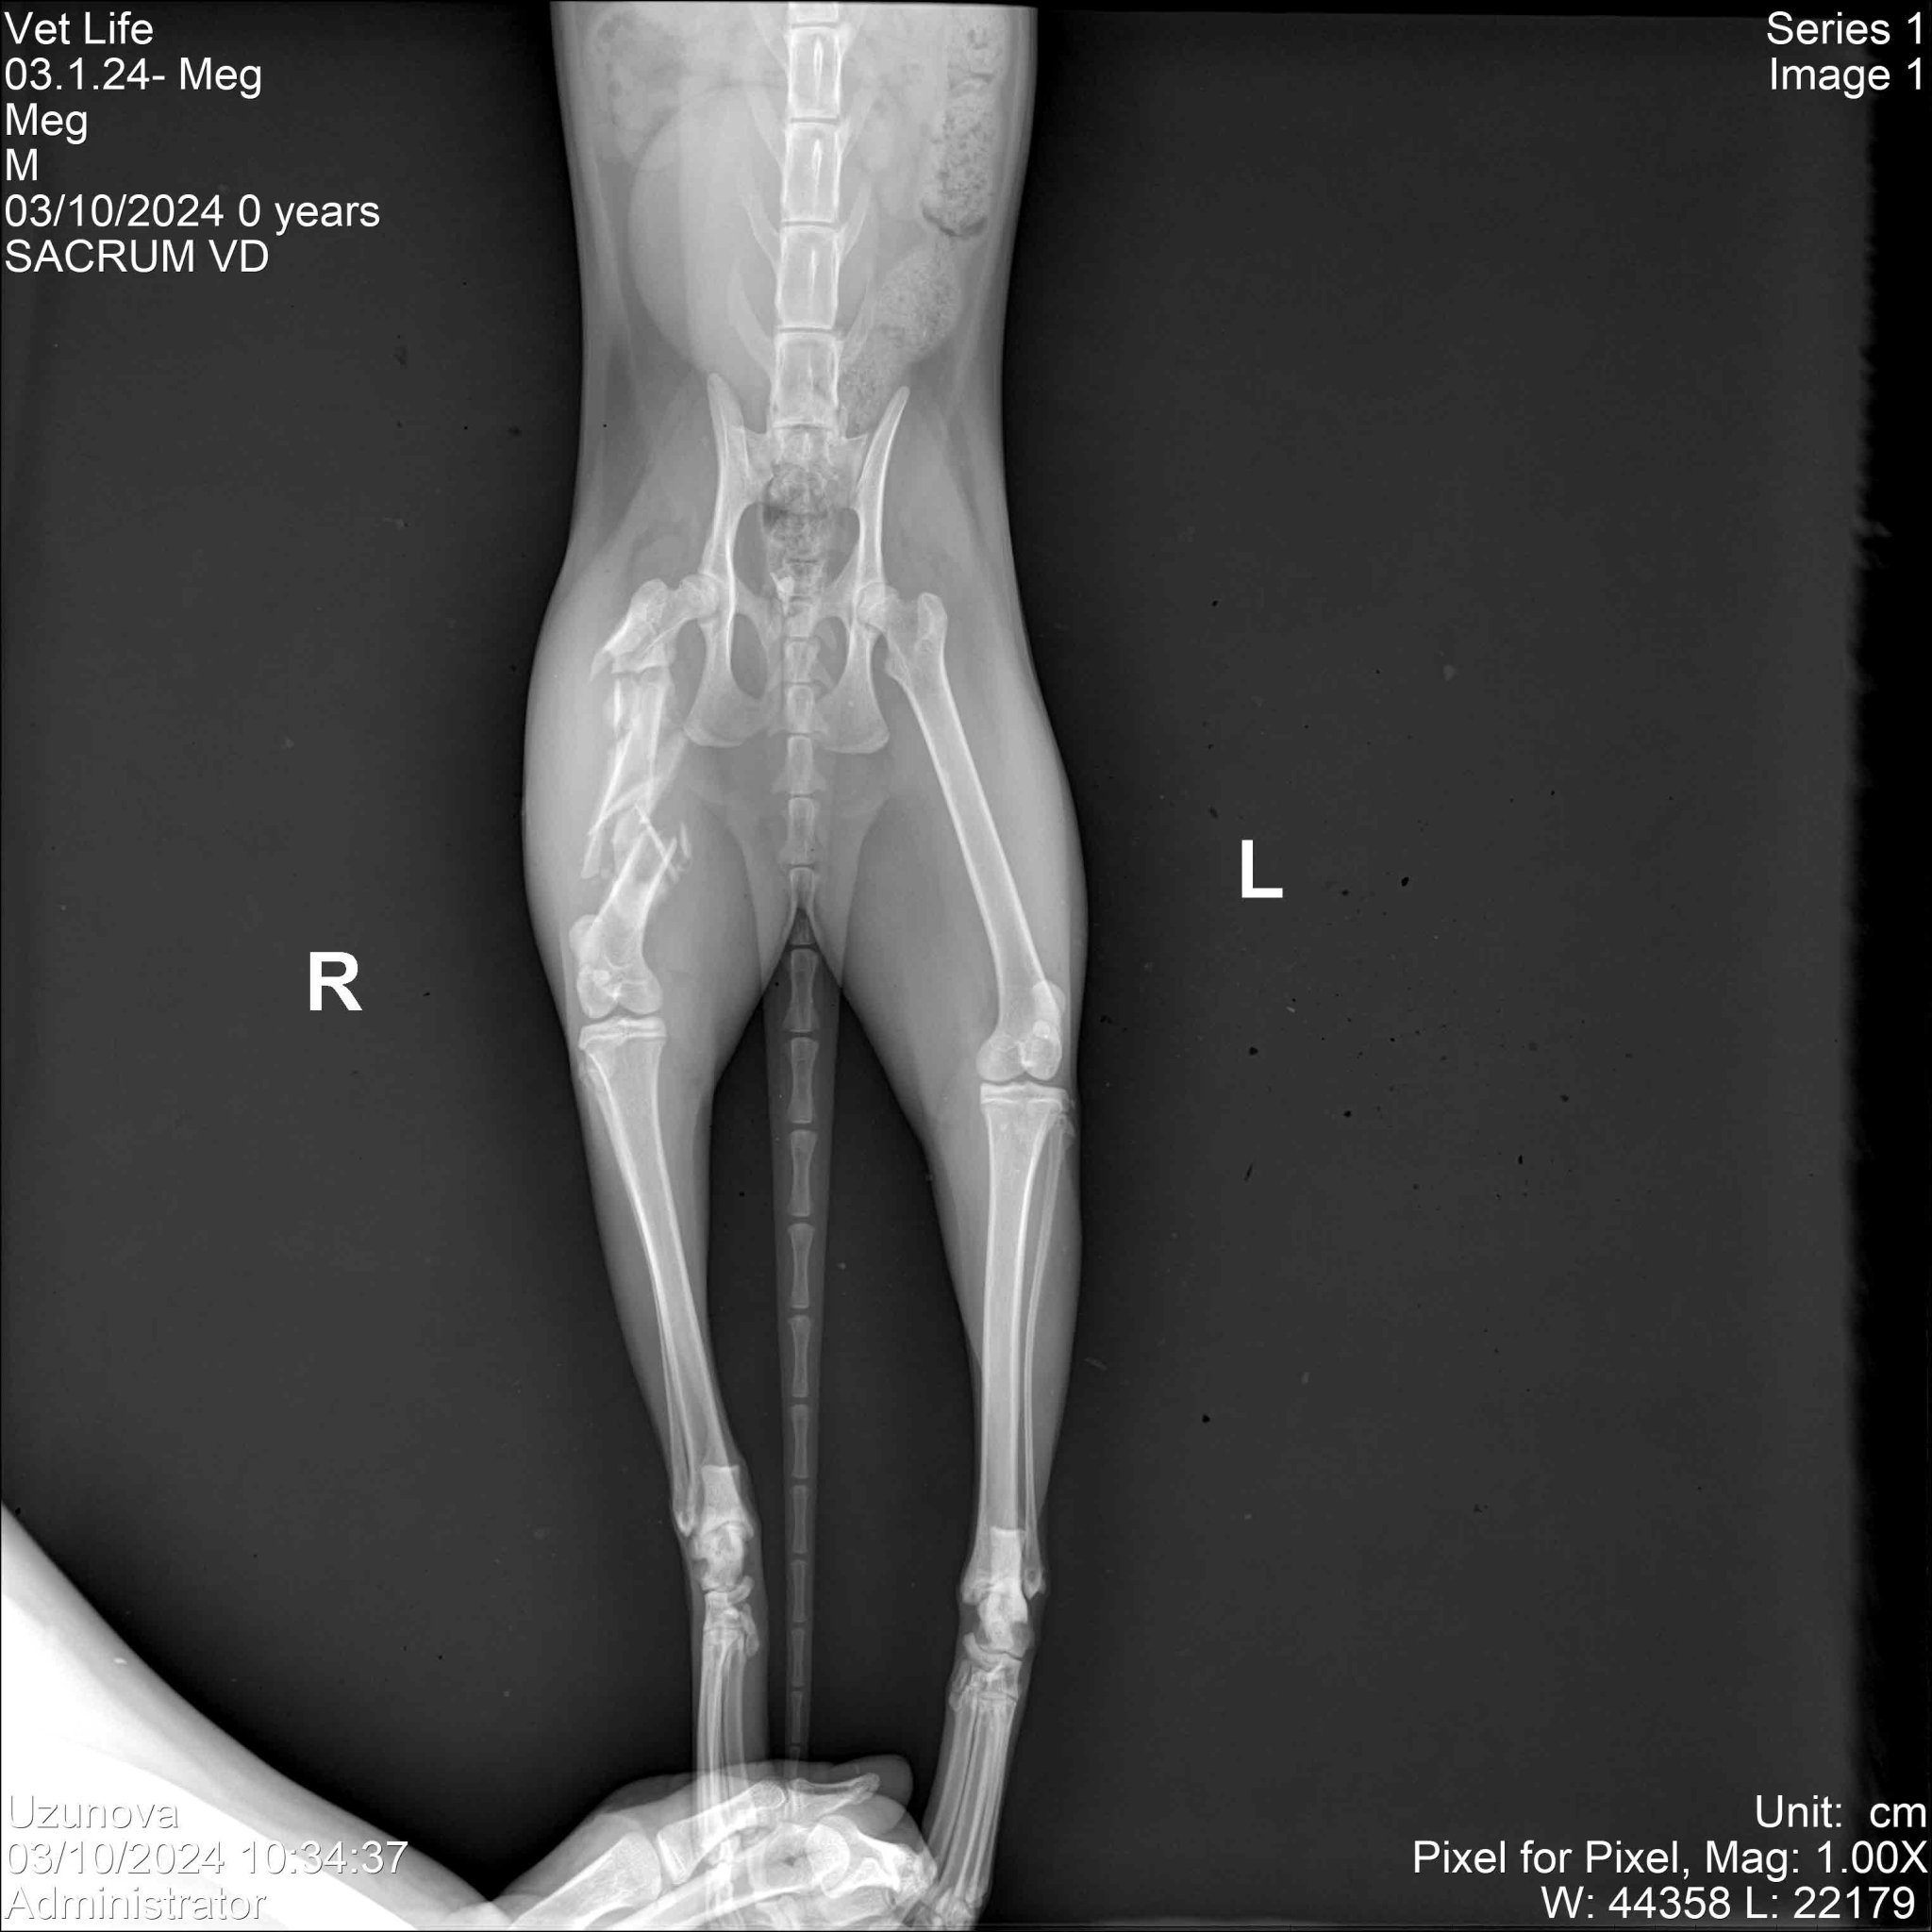

Слагам в скрит текст рентгенована снимка на Мег, за да илюстрирам нагледно, че такова нещо няма как да си зарастне само и по нормален начин. Самото краче беше и подуто, но сега отока е спаднал. Много й харесвам лапичката (тази е беличка, а другата е с чорапче), но не искам да се мъчи цял живот с болно краче.

Не знам колко добре се вижда така, но има множесто парченца.